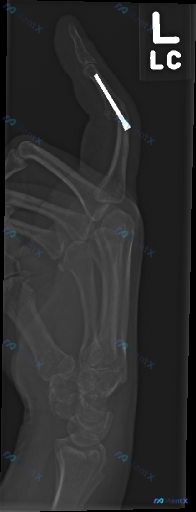

整理到一份左手拇指的术后影像资料,先把客观的影像观察结果放出来,大家第一眼会怎么解读? 影像学客观发现: - 左拇指近节指骨内可见高密度金属内固定钉,沿指骨长轴走行 - 内固定周围骨质结构中,未见明显透亮骨折线,皮质轮廓基本连续 - 掌指关节、指间关节对位关系尚可,关节间隙清晰 - 软组织密度未见明...